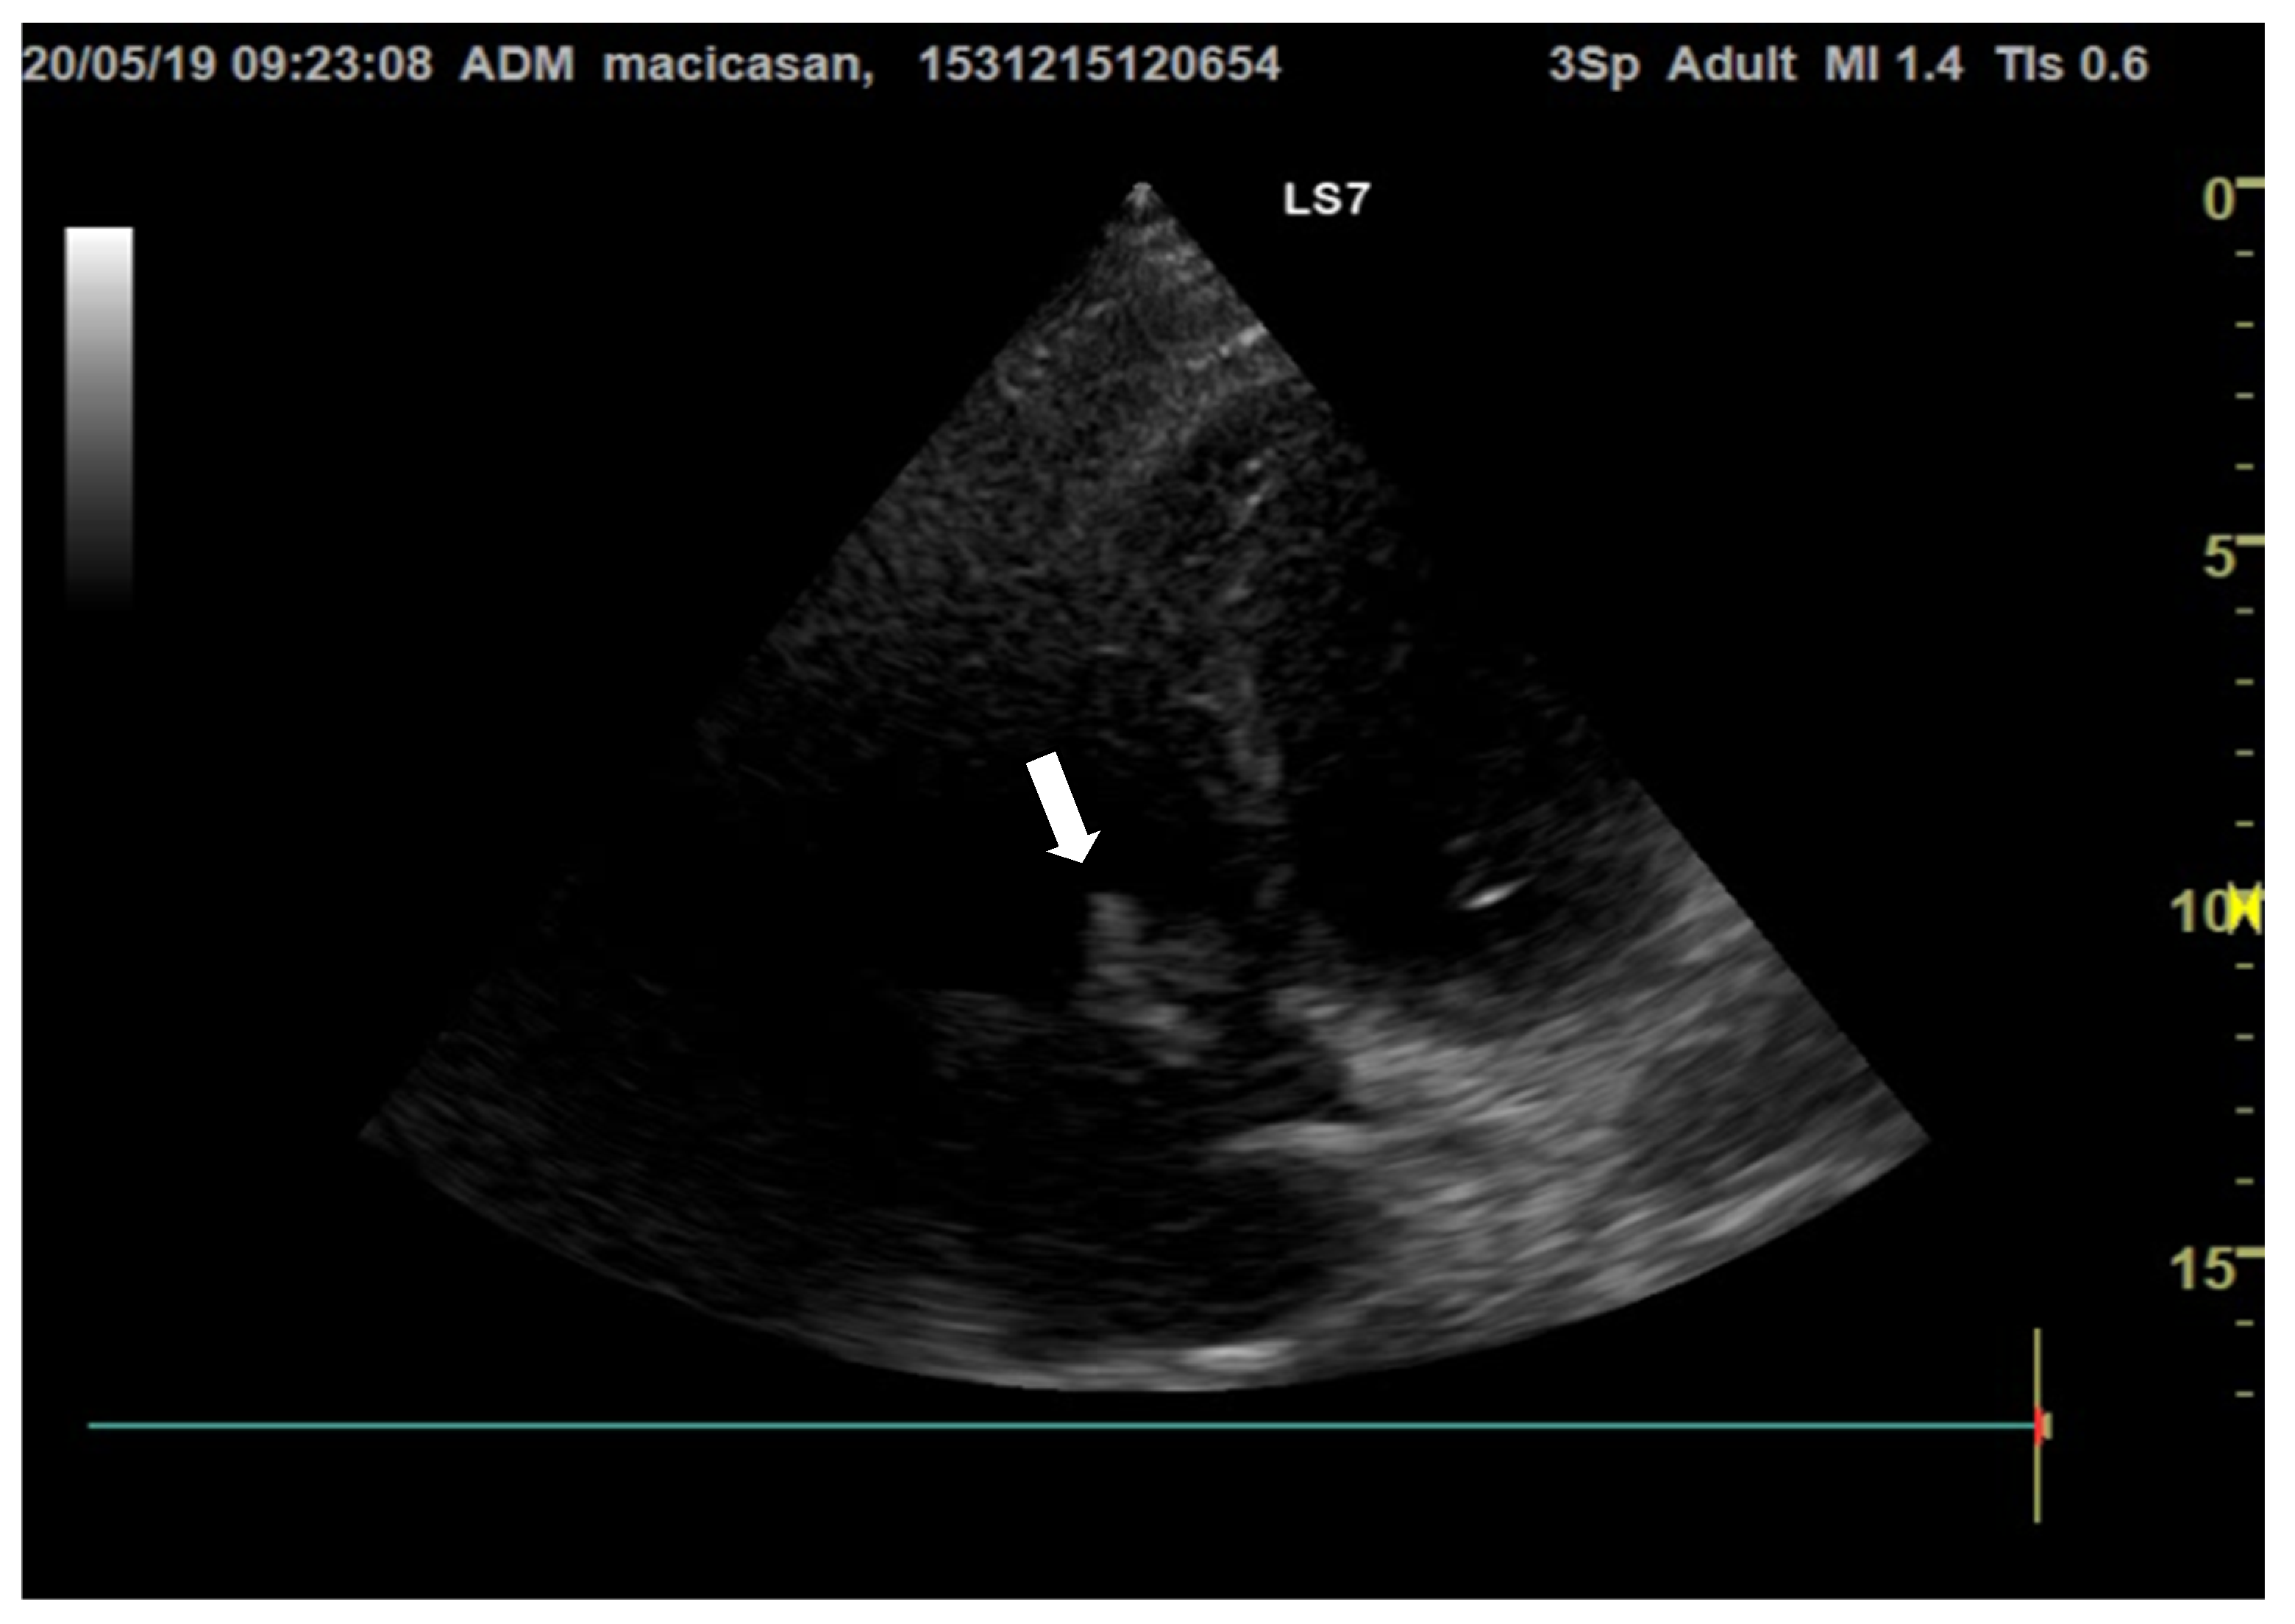

Doppler echocardiography showed a non-dilated left ventricle (LV—55/47 mm), grade III aortic insufficiency with a jet that hit the anterior mitral valve, mobile hyperechoic mass located on the aortic valve (3.5/0.95 cm) and on the tricuspid valve (2.5/1.4 cm), grade II tricuspid insufficiency, moderate secondary pulmonary hypertension (PAPs—50 mmHg), a slightly dilated right ventricle (40 mm sub tricuspid), TAPSE of 22 mm, EF of 50%, and free pericardium (Figure 2 and Figure 3).

Figure 2. Transthoracic echocardiography, apical 4-chamber view, reveals hyperechogenic vegetations on the tricuspid valve (the white arrow is indicating the vegetation on the aortic valve).